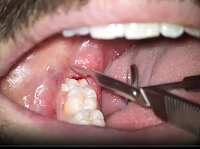

Oral Suergery (Zerodonto Dentistry) 2018

Spécialités : Stomatologie